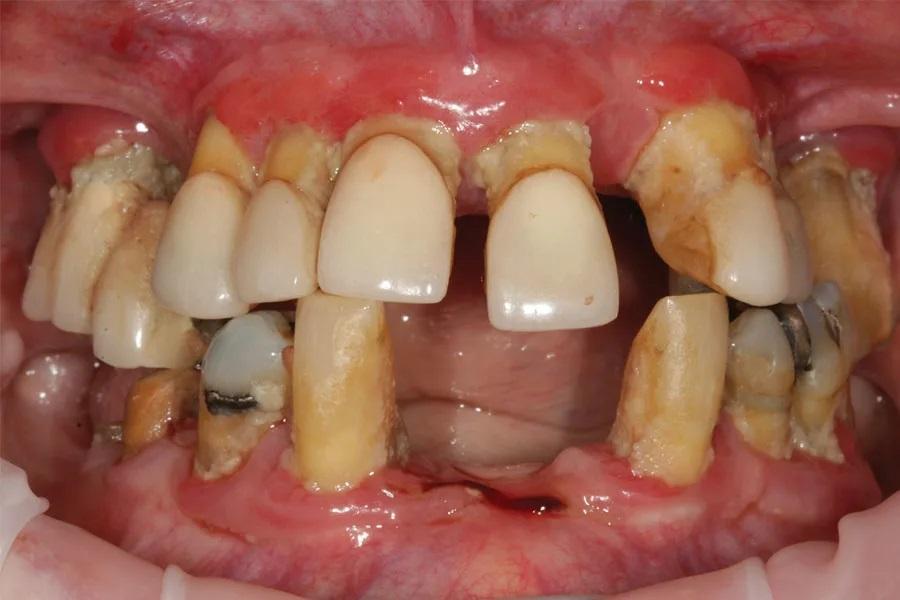

В апреле 2017 года 74-летняя пациентка обратилась с жалобой на то, что «все шатается» (Фото 1 и Фото 2). В анамнезе — гипертония и лечение рака груди в 2002 году с удалением левой молочной железы, но противопоказаний к стоматологическому лечению не было. Пациентка принимала Avapro и Pravachol и имела аллергию на пенициллин.

Фото 1: Клинический случай 1. Состояние пациентки при обращении.

Пациентка испытывала сильный страх перед стоматологическим лечением, что усугубило состояние ее зубов. У нее были частичные съемные протезы на верхней и нижней челюстях, а оставшиеся зубы имели запущенный пародонтит, кариес и подвижность. На панорамном снимке все зубы были признаны не подлежащими восстановлению (Фото 2). Учитывая финансовые ограничения и страх перед хирургическим лечением с установкой имплантатов, было принято решение о цифровом изготовлении немедленных протезов. После заживления тканей временные протезы должны были быть заменены на окончательные. Из-за страха пациентка вернулась к лечению только через 3 года.